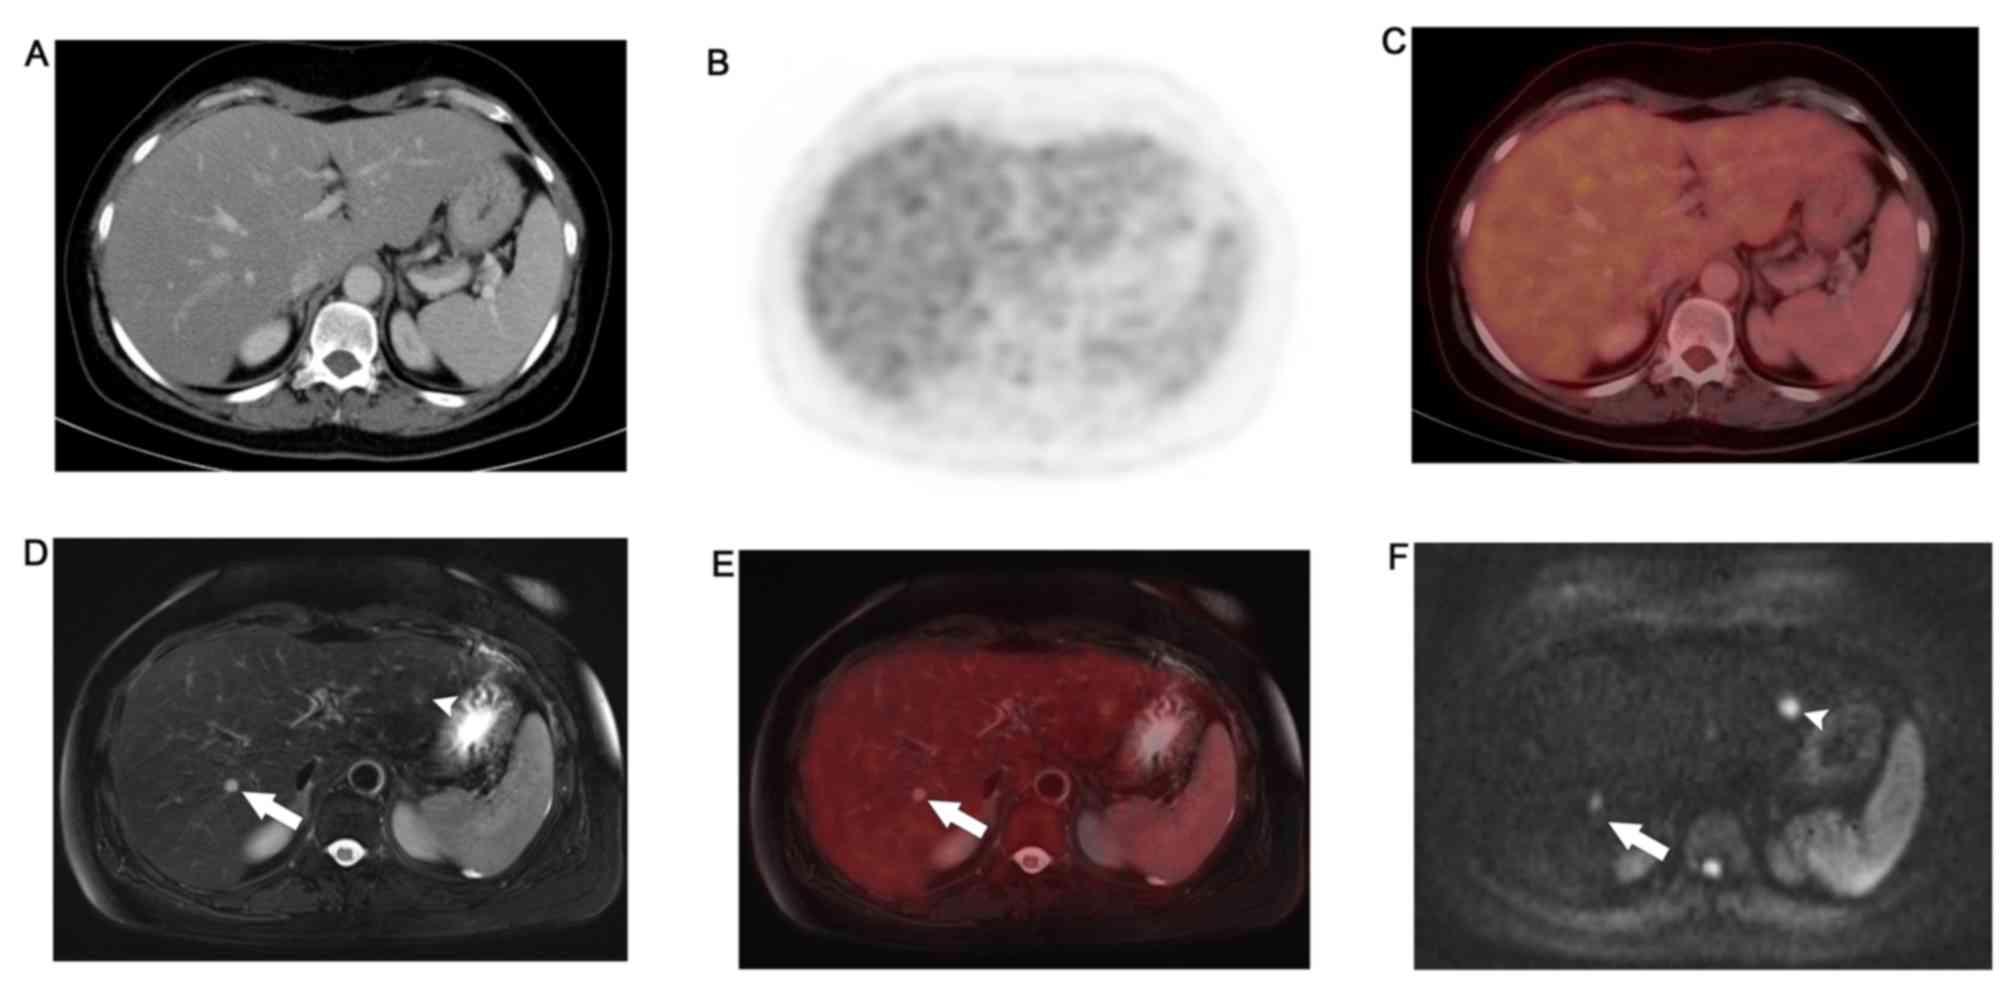

Exported Atypical Liver Hemangioma